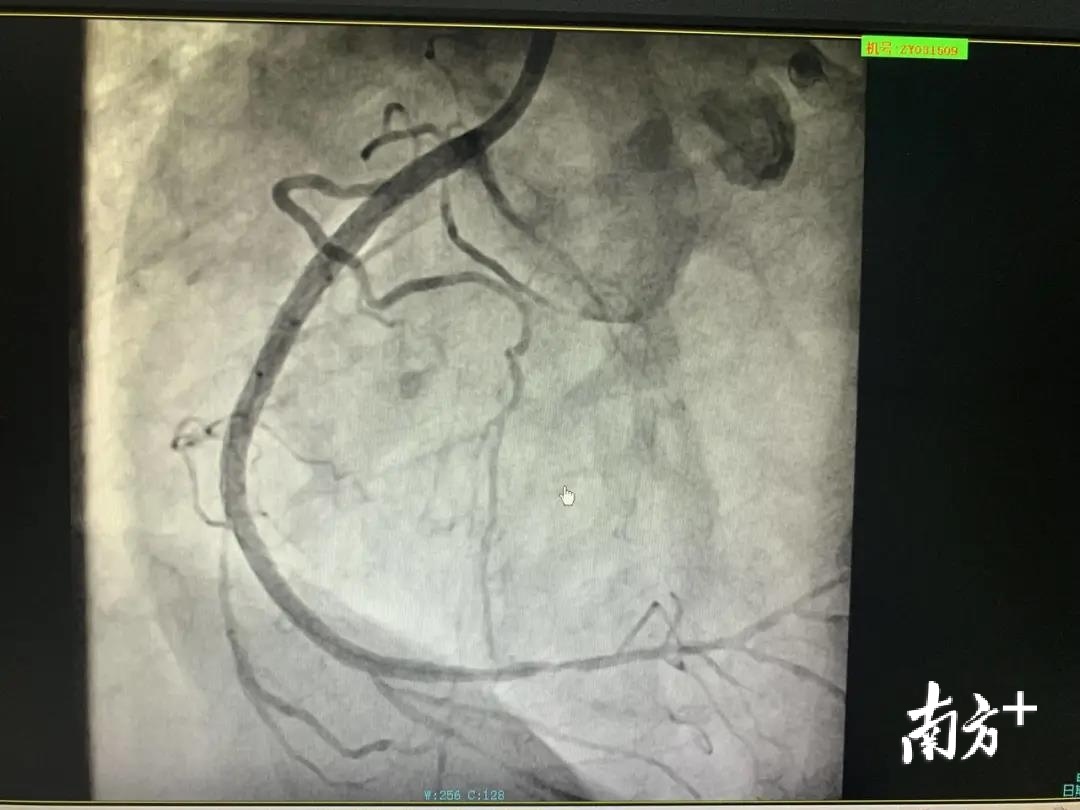

在完成左侧血管支架手术后,钱先生的病情得到了暂时缓解。但因右侧血管堵塞多时,不能正常供血,血管内已经严重钙化,出现了低血压、室速、心脏骤停的情况,被诊断为冠状动脉慢性完全闭塞性病变(CTO),这是冠脉介入治疗领域内难以攻克的堡垒。想要打通这条闭塞多时的血管,难度相当大。

兰军马上启动二次手术,尽早将闭塞的右侧血管打通。他采用目前世界最先进的“逆向导丝开通血管”技术。在距离第一场手术两周后,钱先生接受了第二场手术。在经过100分钟的奋战,心内科团队打通长期堵塞的右侧血管,成功地从死神手里夺回钱先生的生命。